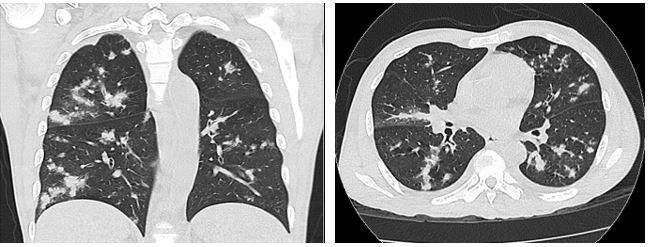

On admission, he was febrile (103.8°F), tachycardic and tachypneic. Physical exam revealed extensive purple-pink skin lesions and lower extremity pitting edema with no clinical signs of cellulitis. Lymph node exam was significant for supraclavicular, axillary, and inguinal lymphadenopathy. Labs revealed hemoglobin of 5.3 g/dl, lactate of 3.5 mmol/L and absolute CD4 count of 19 cell/ul. CT scans of the chest, abdomen and pelvis revealed multiple retroperitoneal and mesenteric lymph nodes, as well as multiple lytic lesions involving the pelvis and thoracolumbar vertebrae. Representative images from the chest CT are shown below.

Images 1 & 2